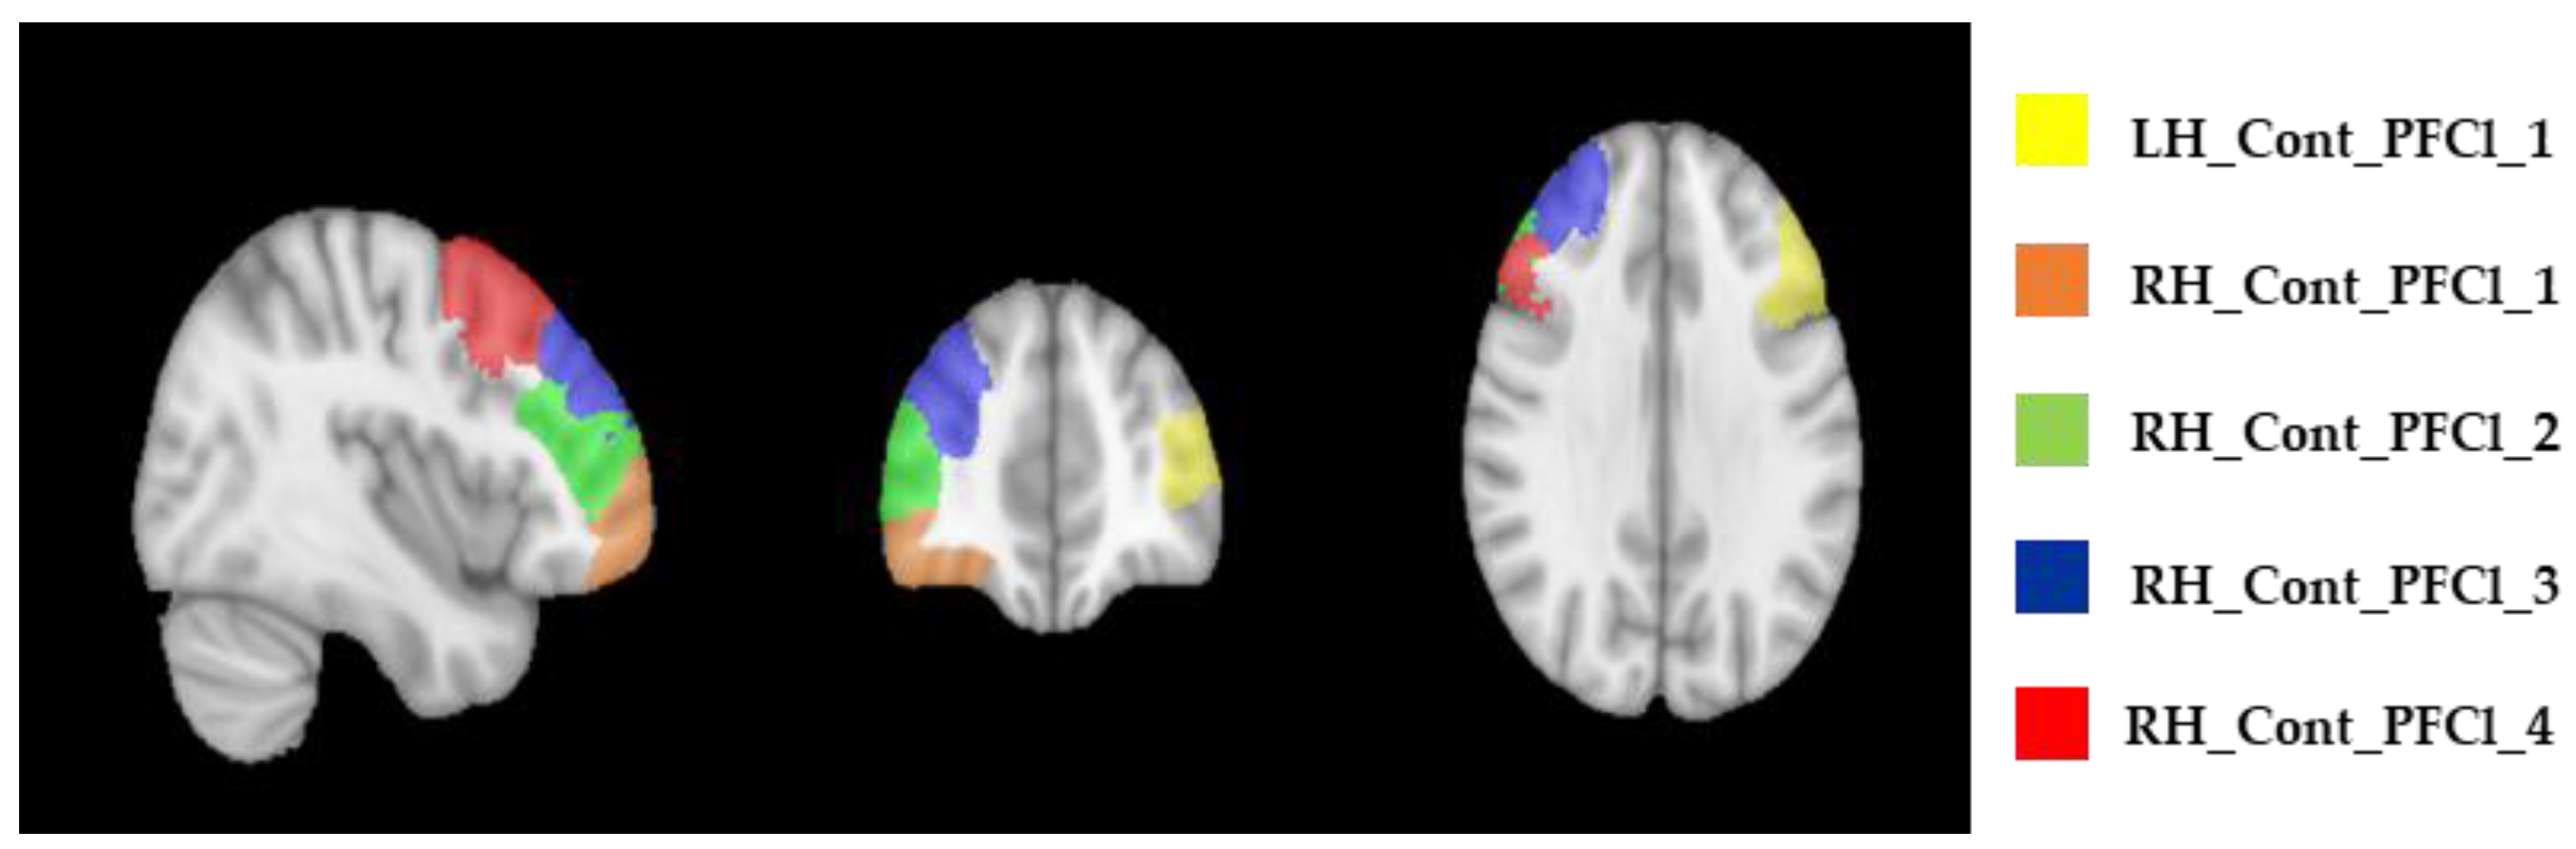

| ROI Labels | Baseline—T0 Median (IQR) | After 4 Weeks—T1 Median (IQR) | After 6 Months—T2 Median (IQR) |

|---|---|---|---|

| LH_Cont_PFCl_1 | 1.30 (1.19–1.32) | 1.26 (1.19–1.31) | 1.24 (1.17–1.34) |

| RH_Cont_PFCl_1 | 1.01 (1.00–1.03) | 1.03 (1.01–1.07) | 1.02 (1.01–1.15) |

| RH_Cont_PFCl_2 | 1.06 (1.03–1.11) | 1.07 (1.05–1.17) | 1.06 (1.02–1.15) |

| RH_Cont_PFCl_3 | 1.13 (1.10–1.18) | 1.16 (1.11–1.25) | 1.13 (1.07–1.22) |

| RH_Cont_PFCl_4 | 1.19 (1.12–1.22) | 1.21 (1.14–1.25) | 1.21 (1.07–1.30) |

| ROI Labels | Baseline—T0 Median (IQR) | After 4 Weeks—T1 Median (IQR) | After 6 Months—T2 Median (IQR) |

|---|---|---|---|

| LH_Cont_PFCl_1 | 1.18 (1.10–1.22) | 1.17 (1.14–1.25) | 1.17 (1.12–1.27) |

| RH_Cont_PFCl_1 | 1.02 (1.00–1.08) | 1.02 (1.00–1.03) | 1.05 (1.02–1.10) |

| RH_Cont_PFCl_2 | 1.10 (1.03–1.19) | 1.03 (1.02–1.15) | 1.08 (1.02–1.11) |

| RH_Cont_PFCl_3 | 1.17 (1.11- 1.22) | 1.07 (1.05–1.19) | 1.11 (1.06–1.13) |

| RH_Cont_PFCl_4 | 1.17 (1.11–1.24) | 1.10 (1.04–1.15) | 1.10 (1.04–1.20) |